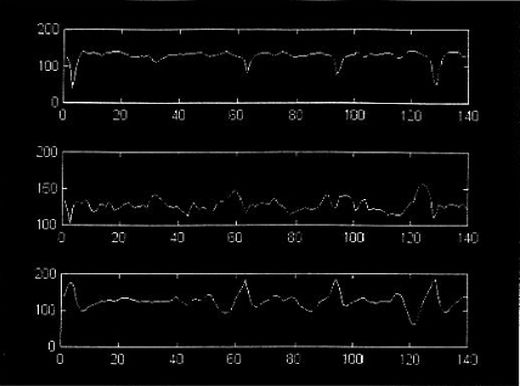

• Fetal Heart Rate Estimation by Doppler Echocardiograph using Cross Correlation

This project is a part of a research dealing with analysis of fetal Doppler echocardiogram in order to diagnose fetal stress.

• Estimation of Fetal Heart Activity

The purpose of this project was to develop a noninvasive method to detect fetal heart activity in utero.